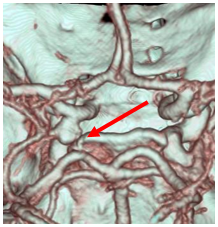

Apoplexy 21

【術前】

Apoplexy 22

【フローダイバーダー留置】

Apoplexy 23

【半年後】

フローダイバーター治療の放射線学的画像

動脈瘤内にコイルを充填することなく、非常に編み目を細かくしたステントで、これを正常血管に留置することで脳動脈瘤内に流入する血液量を減少させます。すると脳動脈瘤内の血液がうっ滞し、徐々に血栓化して脳動脈瘤が完全に閉塞します。半年後に約75%、1年後に約85%が完全に閉塞すると言われています。このような新しい治療法が動脈瘤治療において今後も期待されています。